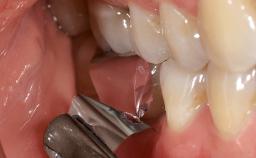

Surgical Management of Peri-Implantitis: Reconstructive Surgical Treatment with Three-Year Follow-up After Treatment

Despite anti-infective surgical treatment, some patients may experience recurrent infection and progressive bone loss requiring additional treatment. Removal of Implant Due to Recurrent Infection describes a conservative approach using an implant retrieval tool without the need for excessive bone removal or use of a trephine.

A 70-year-old female patient was referred by her general dentist to the periodontist for assessment and management of an infection associated with implant 36. The general dentist had noted suppuration on probing during examination.